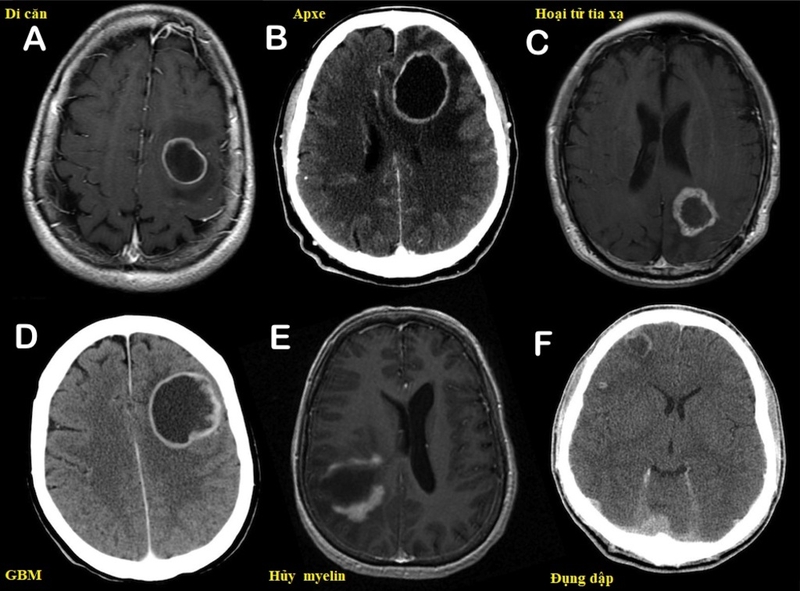

áp xe não 1 Ảnh chụp khối áp xe não ở một bệnh nhân